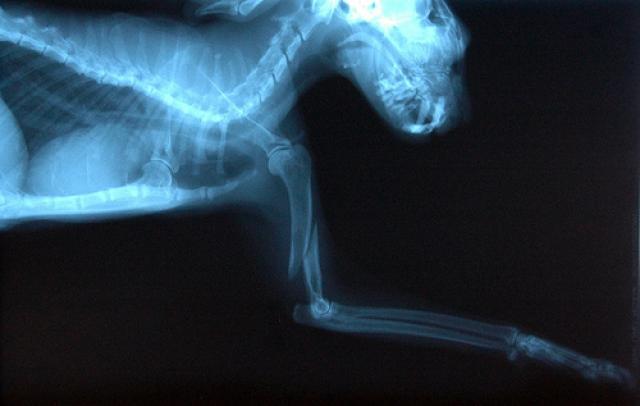

Osteoarthritis in dogs is diagnosed through a physical exam and imaging.

Radiographs (X-ray)